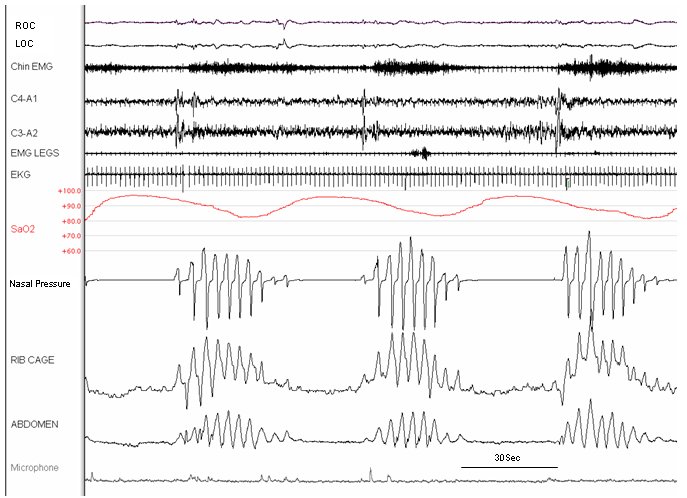

Paroxysmal nocturnal dyspnea. The first tracing shows characteristic central sleep apnea – Cheyne-Stokes respiration (CSA-CSR) with waxing and waning ventilatory effort and airflow and a symmetric pattern of oxygen desaturation-resaturation. Microarousals typically occur during the incremental hyperpnea phase of the CSA-CSR cycle. In some cases, a full awakening may occur, such that the patient arouses at the peak of ventilatory drive and therefore experiences dyspnea, as was the case with the awakening shown on the second slide. Paroxysmal nocturnal dyspnea in a patient with congestive heart failure is an important clinical clue suggesting the presence of CSA-CSR.